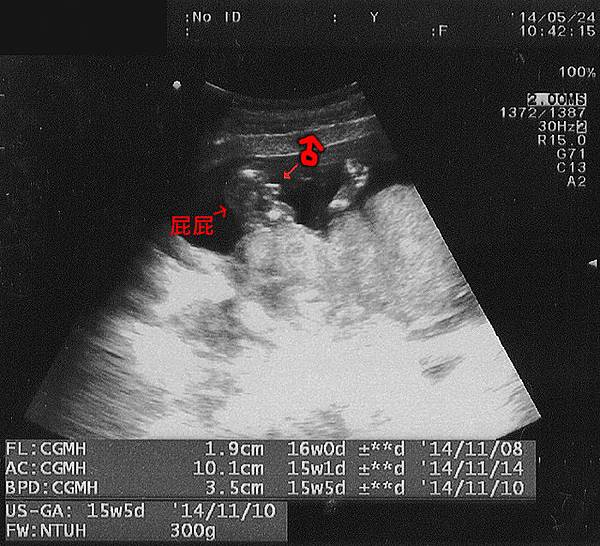

▲超音波照片上寶寶現在是橫躺著,頭在螢幕右邊,腳在左邊

開始照超音波,照例先聽了心跳,醫師說寶寶心跳正常,一分鐘跳一百六十幾下,應該就是超音波照片最下方那個數據 "165PM" 吧?

後來又確認了寶寶的四肢,但速度很快其實我們看不太清楚...就是有看到兩隻腳、兩隻手最突出的亮點,又量了大腿骨長、腹圍、頭骨橫徑(這個數據又換算成體重)。

FL_大腿骨長:1.9cm

AC_腹圍長度:10.1cm

BPD_頭骨橫徑:3.5cm

FW_體重:300g

以上大致都正常,只有腹圍稍微小了些

▲從屁屁下方的角度照,清楚看出有凸出物...

最後醫師主動要找寶寶的性徵,本來說兩腿夾住看不出來,然後就隔著我的肚皮在寶寶的腳那個位置用超音波那隻嚕了幾下,寶寶的腿就動了幾下張開了。明顯看出有凸出來的部分,醫師說應該是男生,然後就結束這次的超音波。我躺著看到Robert失望的神情,呵呵...他本來比較期待女孩,因為覺得男生會比較皮,女生比較貼心。